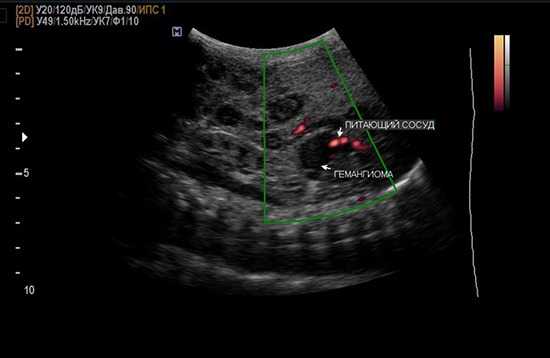

Опухоль может затрагивать как один, так и несколько сегментов печени. Сверху гемангиома окружена фиброзной капсулой, которая отделяет опухоль от паренхимы печени. Обычно новообразование питается кровеносным сосудом, чаще всего это печеночная артерия и её ветви. Размеры опухоли могут варьироваться от 2 см до 20 см. Образования размером до 5 см считаются небольшими, и в таких случаях лечение, как правило, не требуется.

- Ультразвуковое исследование, которое отличается своей доступностью, низкой инвазивностью и достаточно высоким уровнем информативности — при диагностике кавернозной гемангиомы он достигает 80 %. УЗИ позволяет определить факт наличия гемангиомы, ее расположение и размеры. Чтобы определить степень поражения опухолью сосудов, параллельно проводят допплерографию.